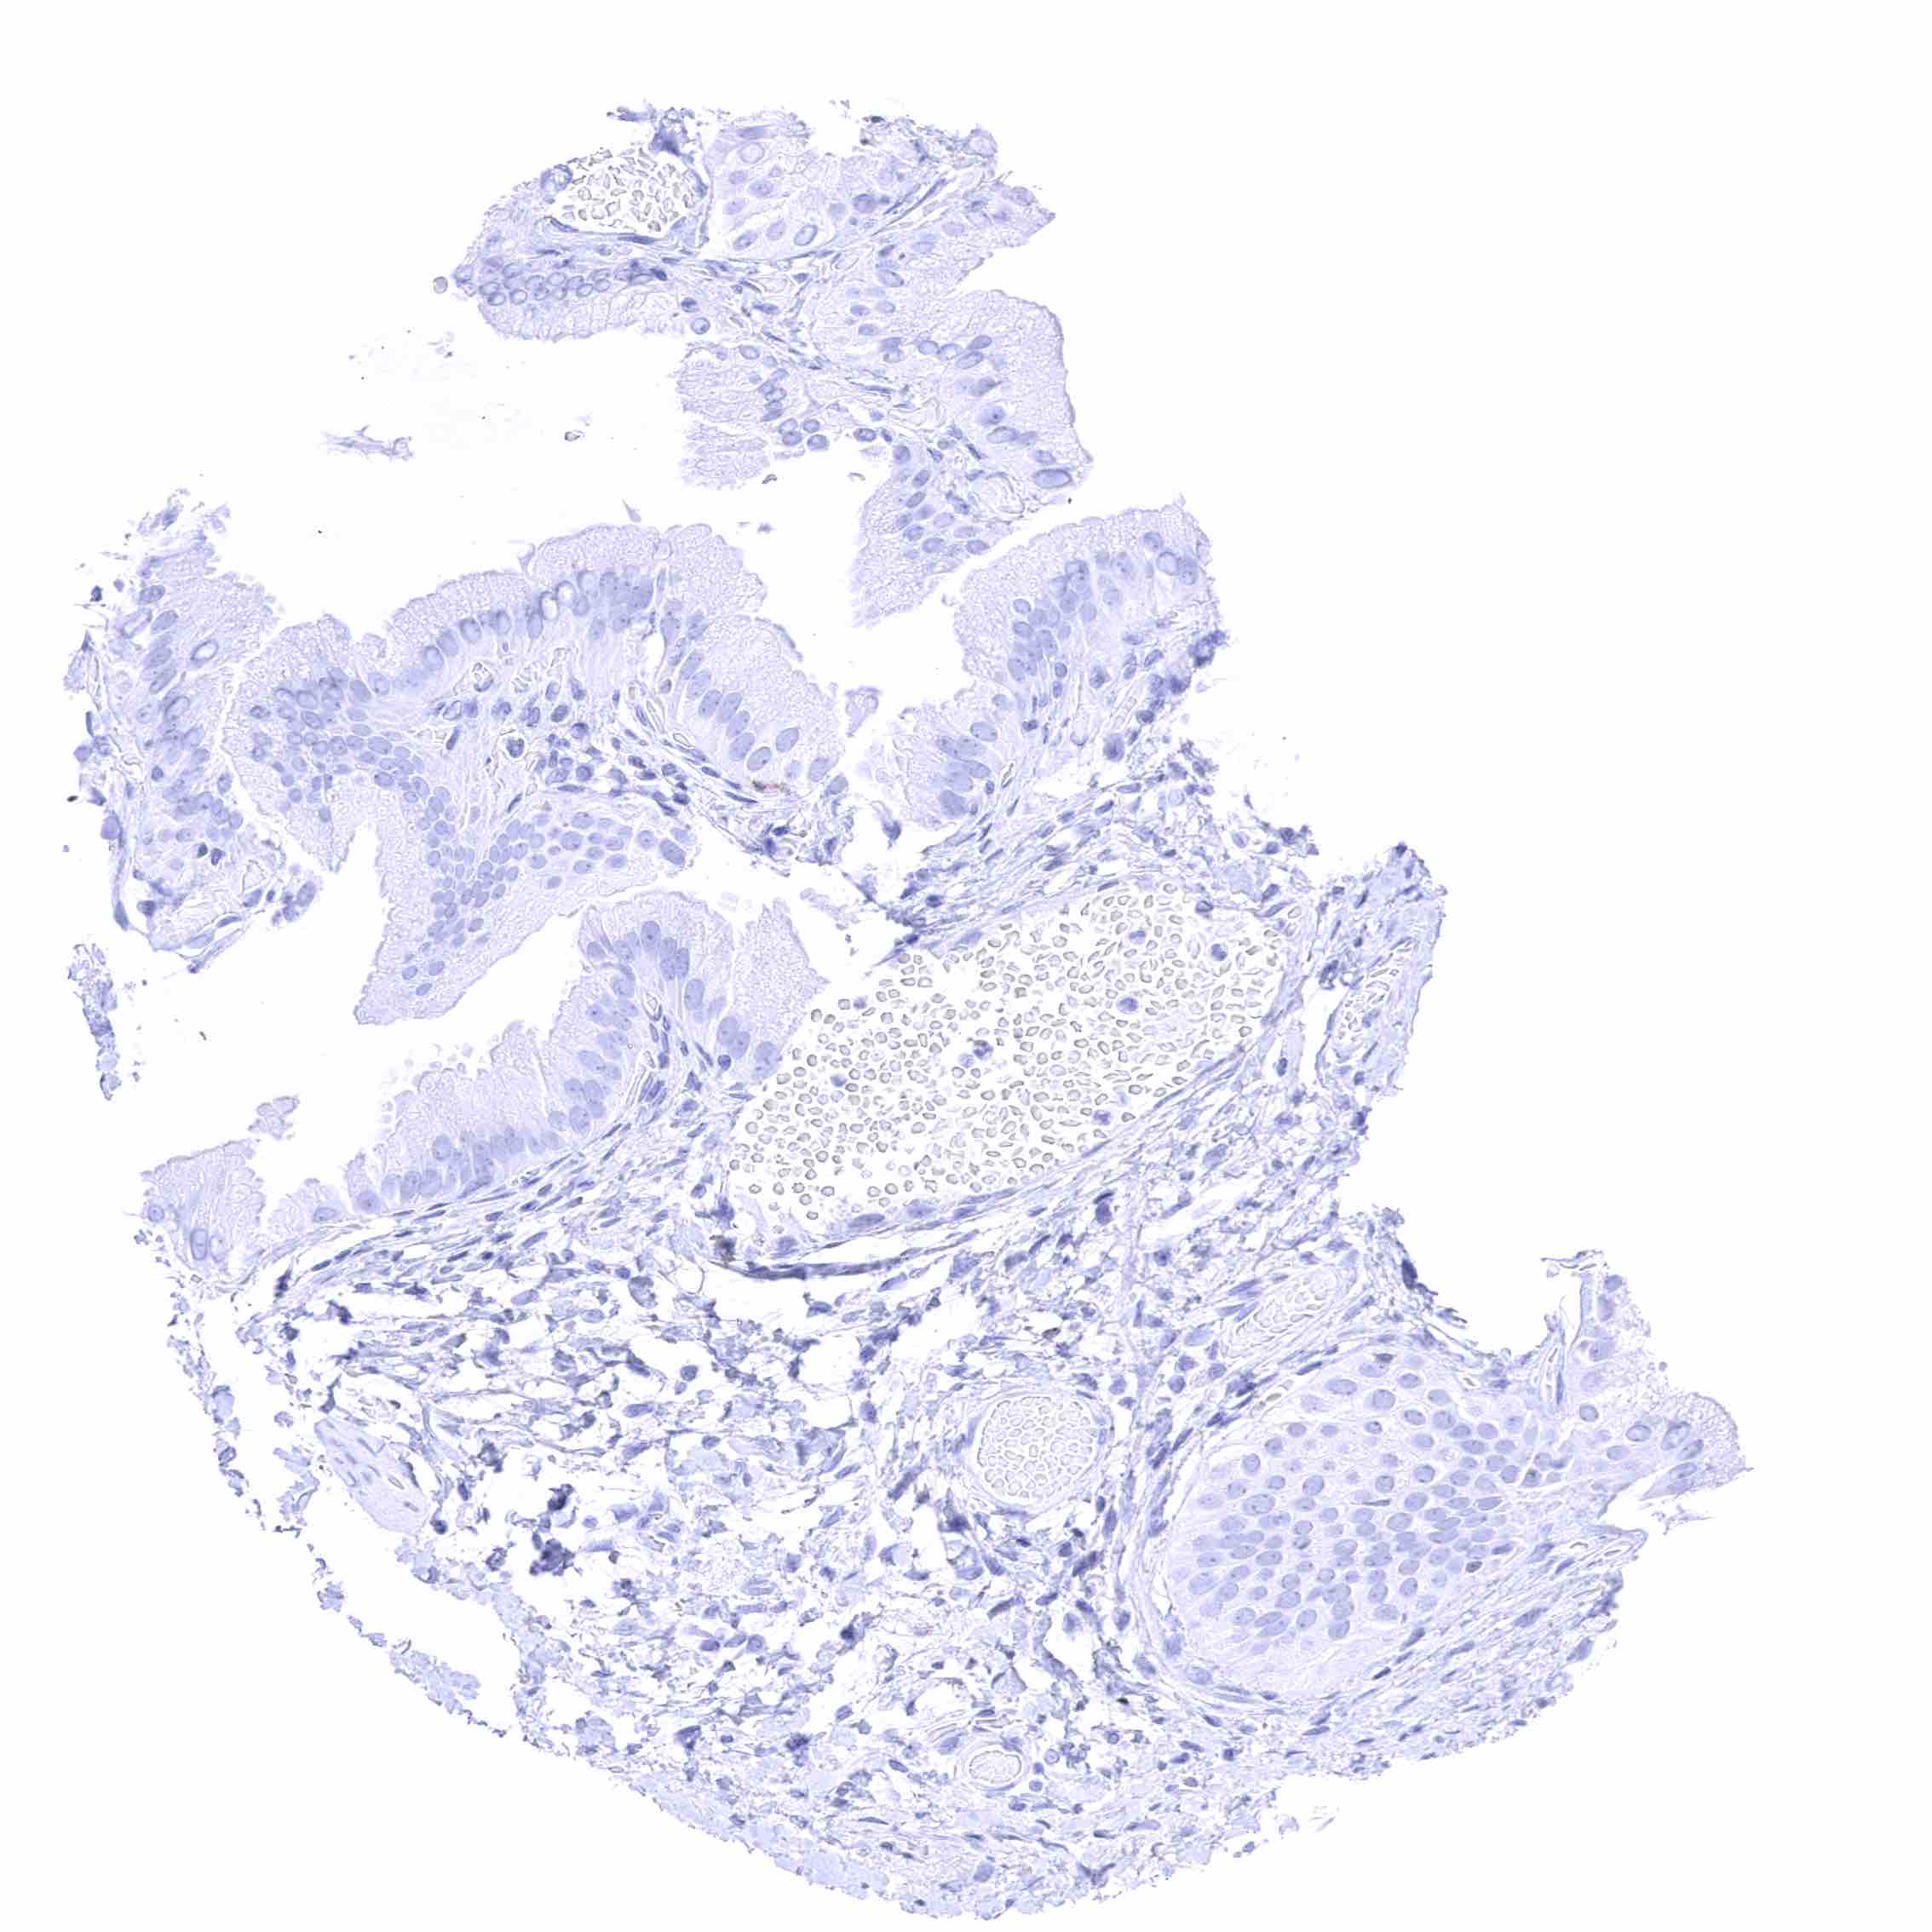

Tonsil – Membranous CD70 staining of variable intensity in subsets of cells (mostly lymphocytes). Most CD70 positive cells are interfollicular.

Tonsil, surface epithelium – Membranous CD70 staining of a subset of lymphocytes while squamous epithelium remains negative.